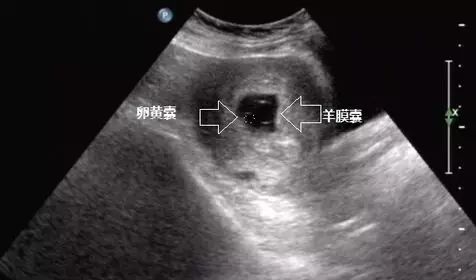

三、双泡征

这里说的双泡征是指早孕的,而不是中晚孕看的十二指肠闭锁的双泡征。内细胞团分裂、分化形成充满液体的羊膜囊、卵黄囊以及胚盘,组成了复合体回声(双泡征)由于囊胚及羊膜腔的快速发育。“双泡征”仅为一过性表现,孕7周后不再出现。

简单说:就是妊娠囊里出现了两个泡状结构。一个是卵黄囊,一个是羊膜囊。